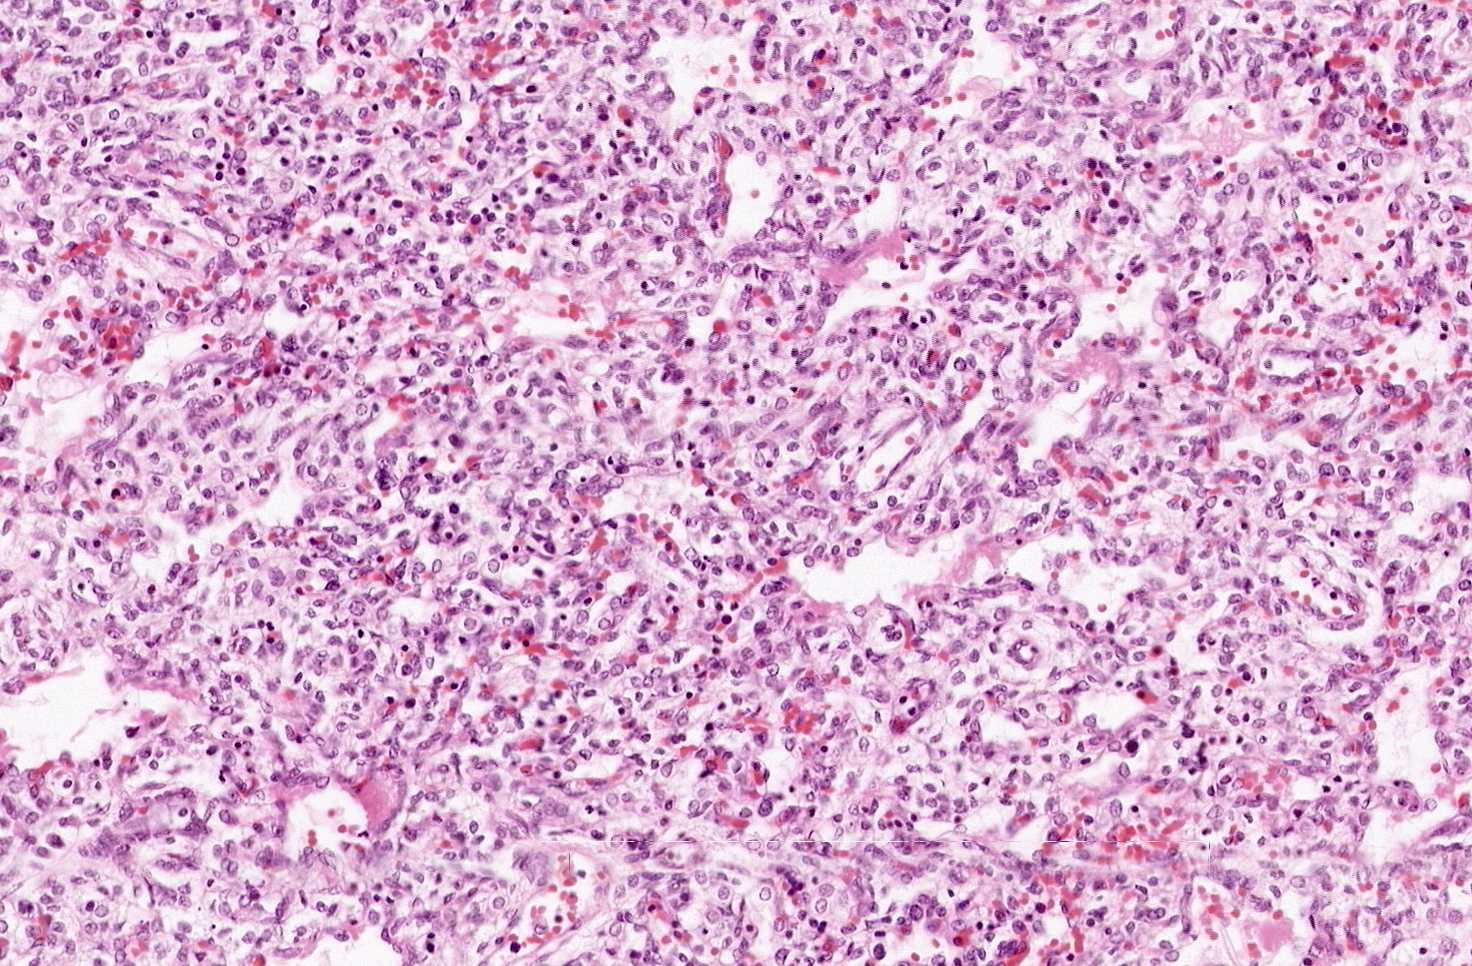

Area 2: In this area, you can see that most of the air spaces are not fully dilated. There are some more dilated spaces and you can find some pale eosinophilic substances lining these spaces. These are the hyaline membranes.

• What organ is this? From the histologic perspectives for medical students, the first goal is to identify the organ of this slide. At the scanning level, it looks partially solid but there are some small slits in between. There are also some tubule like structures (arrow). On a closer look, these tubules are lined by ciliated columnar epithelium and some may have cartilage next to it and these are bronchi/bronchioles. On higher magnification, you can appreciate that the solid looking areas are in fact immature pulmonary alveoli that has not fully expanded which end up giving this kind of solid look at low magnification. The alveolar space can be clearly recognized.

• In general, there is no inflammatory cell infiltration and the alveolar spaces are only partially expanded or not expanded at all.

• Although the alveolar spaces are not completely expanded, distal airways and proximal air spaces (alveolar ducts) are usually dilated and lined by a thin layer of delicate, pale eosinophilic, amorphous transuduate-like substance known as hyaline membrane. The hyaline membrane may form within 30 minutes after birth.